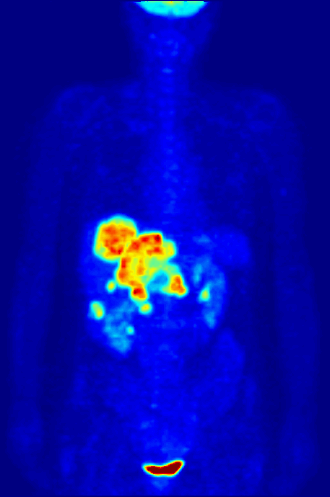

PET — Maximum Intensity Projection Animation

Rotating maximum intensity projection (MIP) of PET scan showing metabolic activity throughout thorax

PET Downloaded 2026-03-15

Pet

Fdg Mip

Wikimedia Commons: PET-MIPS-anim.gif